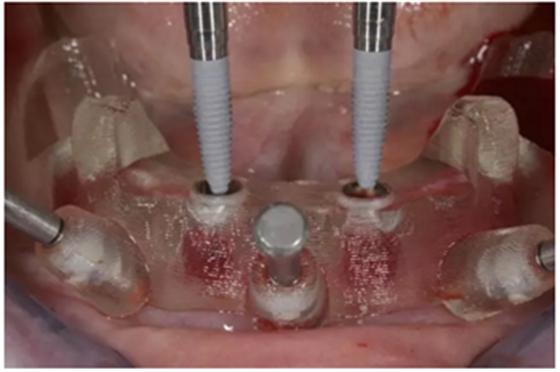

使用內(nèi)錐形連接引導(dǎo)式持釘器在下頜前牙區(qū)植入NobelReplace CC植體。

4枚NobelReplace CC植體均已植入完成:前牙區(qū)植入NP 3.5*13mm植體并裝配引導(dǎo)式基臺以固定導(dǎo)板,后牙區(qū)植入RP4.3*16mm植體并裝配內(nèi)錐形連接引導(dǎo)式持釘器。